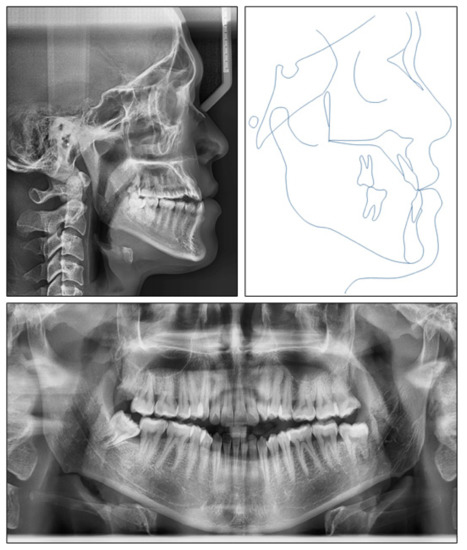

3. Results